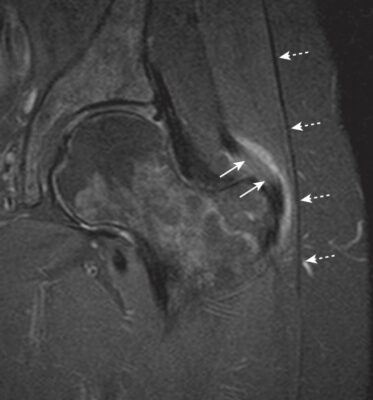

Chụp cộng hưởng từ có thể hữu ích trong trường hợp đau mặt bên háng nghi do những nguyên nhân khác. Các thay đổi trên hình ảnh MRI thường quan sát ở các bệnh nhân không triệu chứng do đó giải thích kết quả phải liên hệ với lâm sàng.

Hình ảnh MRI T2 xung xoá mỡ mặt phẳng trán một bệnh nhân đau mặt ngoài háng và viêm túi thanh mạc với tăng tín hiệu do dịch giữa dải chậu chày (mũi tên chấm trắng) và gân cơ mông nhỡ (mũi tên trắng)